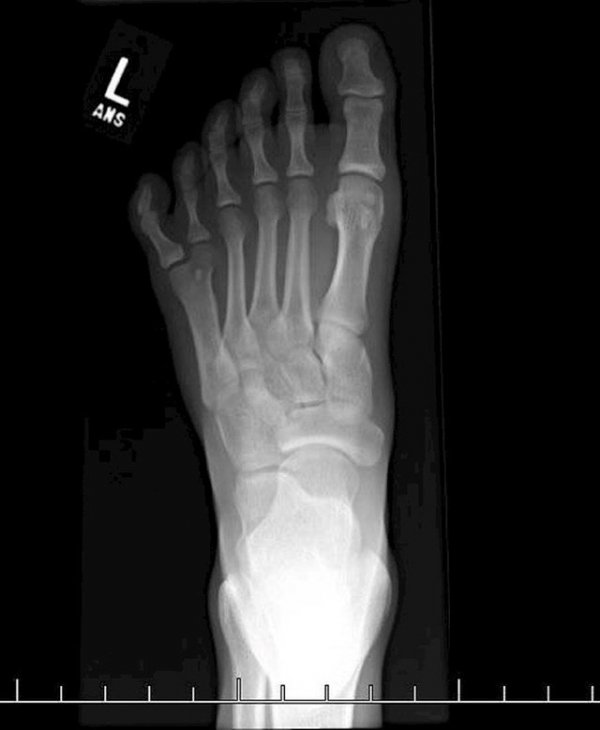

9.Ovako izgleda rendgenska snimka stopala sa šest prstiju.

rendgen-6-prstiju